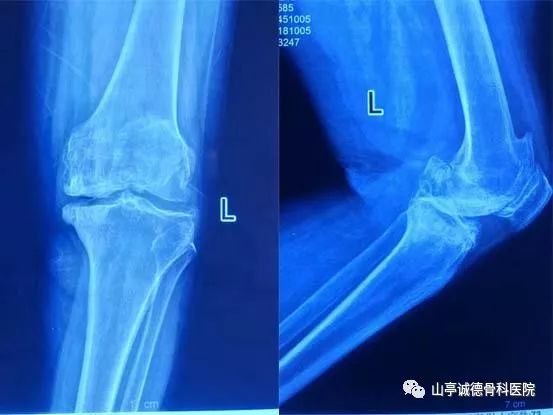

術前X線片可見左側骨質增生明顯